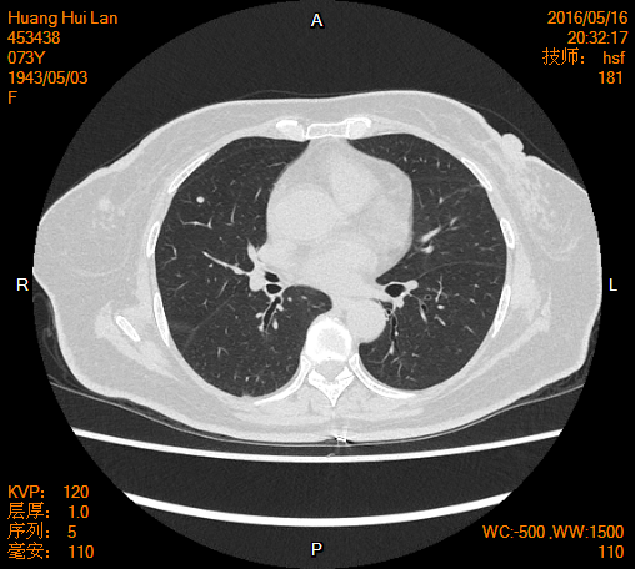

2016-04-13胸腹盆CT

2016-05-17胸腹盆CT(术后基线)